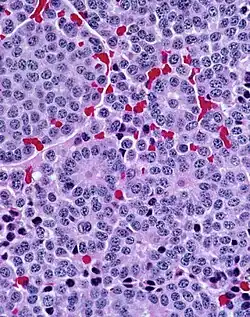

A carcinoid (also carcinoid tumor) is a slow-growing[1] type of neuroendocrine tumor originating in the cells of the neuroendocrine system. In some cases, metastasis may occur. Carcinoid tumors of the midgut (jejunum, ileum, appendix, and cecum) are associated with carcinoid syndrome.

Carcinoid tumors are apudomas that arise from the enterochromaffin cells throughout the gut. Over two-thirds of carcinoid tumors are found in the gastrointestinal tract.[7]

They were first characterized in 1907 by Siegfried Oberndorfer, a German pathologist at the University of Munich, who coined the term karzinoide, or "carcinoma-like", to describe the unique feature of behaving like a benign tumor despite having a malignant appearance microscopically. The recognition of their endocrine-related properties was later described by Gosset and Masson in 1914, and these tumors are now known to arise from the enterochromaffin (EC) and enterochromaffin-like (ECL) cells of the gut. Some sources credit Otto Lubarsch with the discovery.[10]